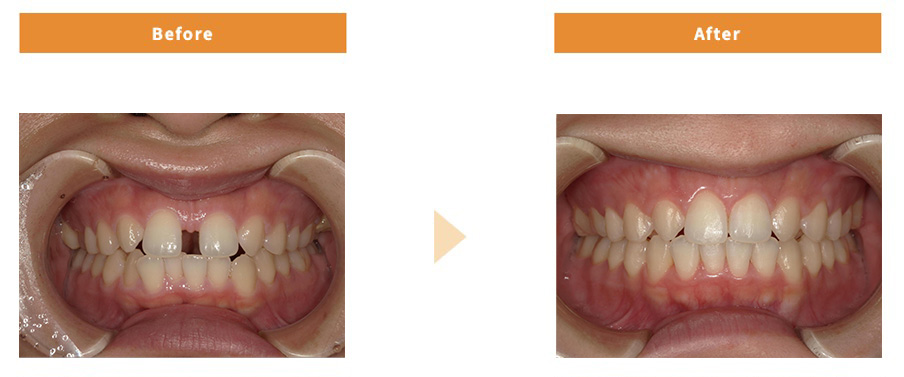

ワイヤー矯正

| 治療費用 | 836,000円 |

|---|---|

| 治療期間 | 1年半 |

| 患者様の主訴 | 上の前歯の隙間が気になる |

| 治療内容 | ワイヤー矯正 |